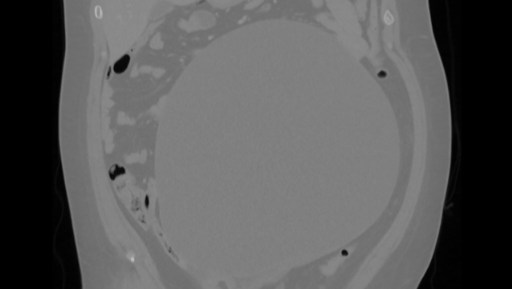

My name is Julieta. I’m currently in Canada and recently received heartbreaking medical news — I have a 25 cm cyst on my right ovary that could rupture at any moment. I also have another smaller cyst, about 3.8 cm on my left ovary.

A few days ago, I had to be admitted to the emergency room because of severe abdominal pain. I initially thought it was related to IBS (Irritable Bowel Syndrome), but after several tests and scans, the doctors discovered the true cause, the large ovarian cyst that’s now putting my health at serious risk.